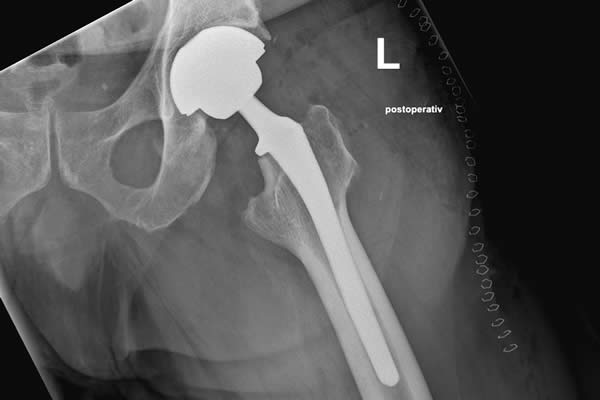

....hoffe ich jedenfalls. Seit vorgestern habe ich eine neue Hüfte, wie der Volksmund so sagt. Tatsächlich heißt das Ding TEP - Totale Endoprothese. Statt eines Oberschenkelhalses trage ich jetzt also TEP, statt Knochen eine Titaniumlegierung, statt Knochengelenk nebst Gelenkschmiere jetzt Keramikkugel in PE Schale. Guckt man sich die Teile im letzten Post so an und fängt an nachzudenken, wie die Ersatzteile dahin kommen, wo sie hin sollen, ist schnell klar, dass das auch alles ein bisschen eckelig ist und viele Teile im Oberschenkel da erstmal Platz machen mussten, damit der alte Kram raus und die neue Technik eingebaut werden konnten. Dementsprechend war einen Tag später auch nicht viel mehr drin, als meinem neuen Gelenk mal die Raucherecke zu zeigen. Ich stehe hier noch mächtig unter Drogen und freue mich über jeden Schmerz, der nachläßt.

Hier mal ein Blick auf mein neues Inlay: